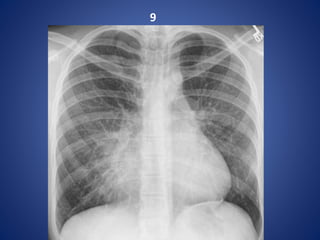

9

Pectus excavatum

Pectus excavatum (or funnel chest) is a congenital chest wall deformity characterised

by concave depression of the sternum, resulting in cosmetic and radiographic

alterations.

Radiographic features

Plain film

Characteristically demonstrates :

• blurring of right heart border (PA or AP film)

• increased density of the inframedial lung zone

• horizontal posterior ribs

• vertical anterior ribs (heart shaped)

• displacement of heart towards the left

• obliteration of the descending aortic interface

CT

The diagnosis is obvious on CT with the degree of

deformity and mediastinal shift often dramatic.

The Haller index (maximal transverse diameter/

narrowest AP length of chest) is used assess

severity. Normal Haller index is 2.5. Significant

pectus excavatum has an index greater than 3.25.